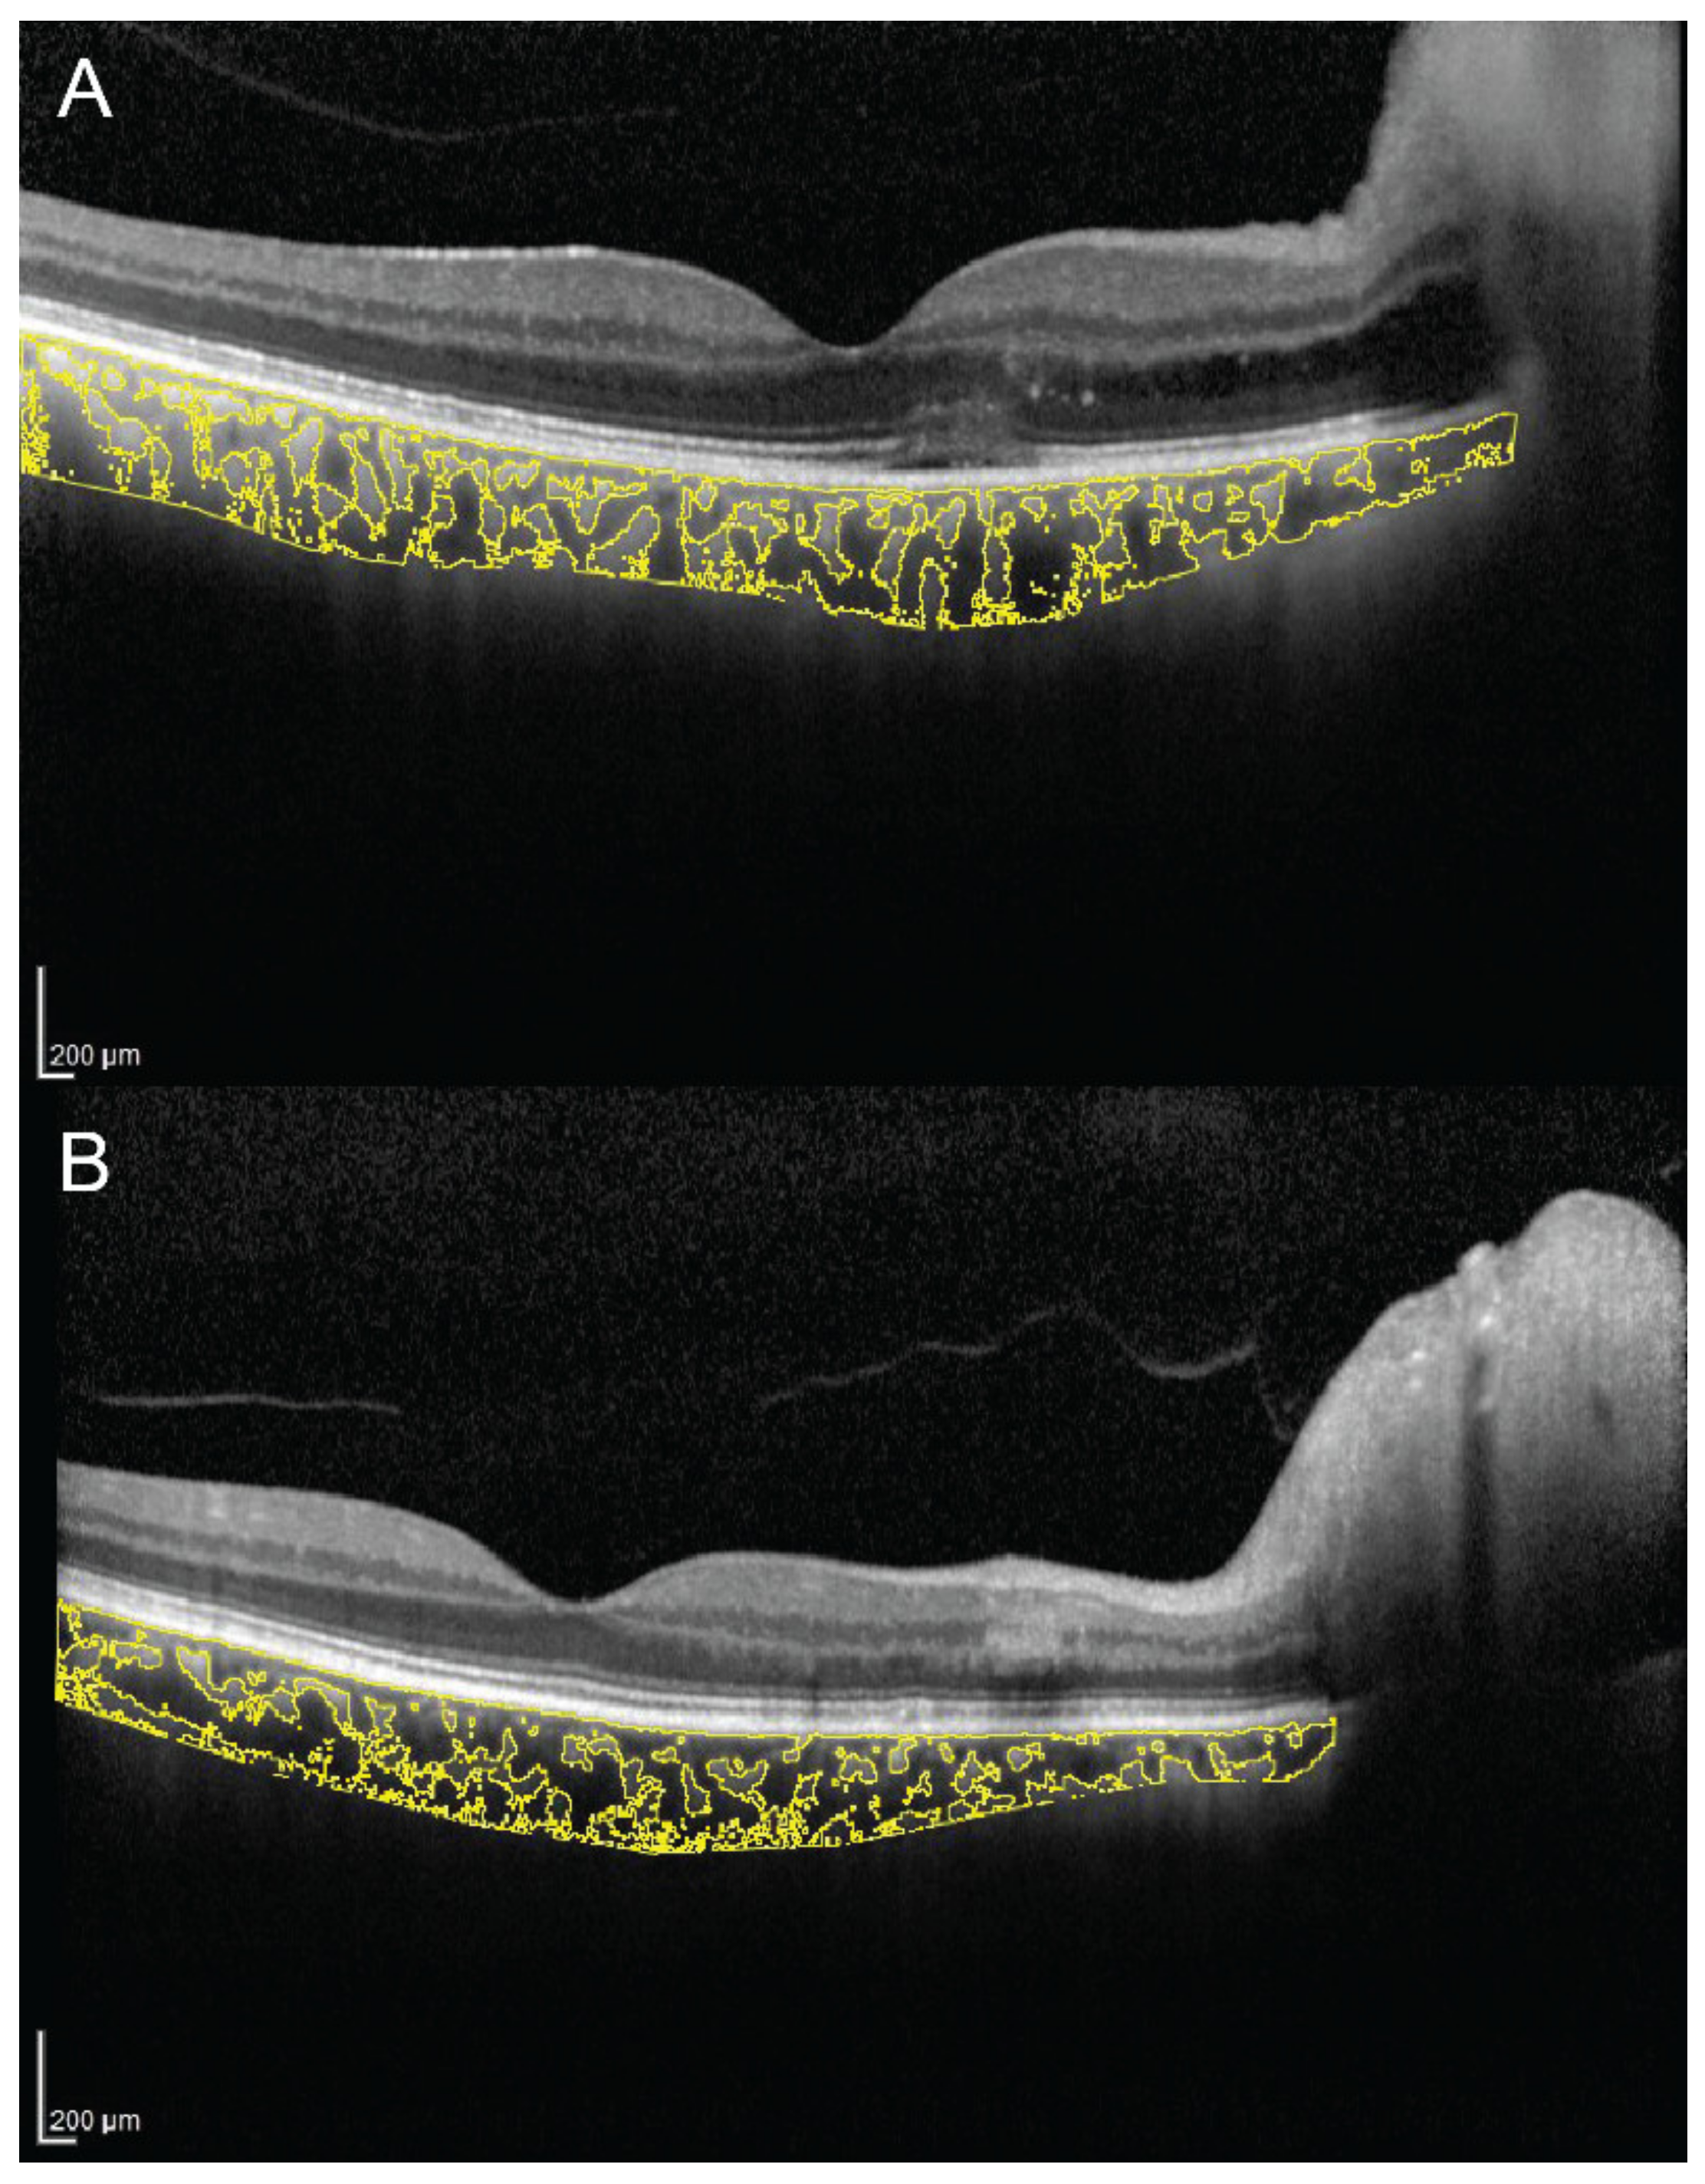

Additionally, CVI was evaluated to compare the effect of full-dose, half-dose (full fluence) and half-dose half-fluence photodynamic therapy (PDT) in CSC [47]. At 3-month follow-up in full-dose and half-dose (full fluence) group, CVI decreased and visual acuity improved significantly. The evaluation of CVI in a representative case of a 56-year-old man with chronic CSC, before and 3 months after half-dose full-fluence PDT, is shown in Figure 3. Conversely, in the half-dose half-fluence group it was significantly increased but no significant visual acuity improvement was recorded. The reduction of subfoveal CT after PDT was statistically significant in all three groups. The results of this study suggest that the effect of PDT on the half-dose half-fluence group was less clear than in the other groups [47].

Figure 3.

Choroidal vascularity index, calculated by the means of automated algorithm in a 56-year-old man with chronic central serous chorioretinopathy (CSC), before (A,B) and 3 months after (C,D) half-dose full-fluence photodynamic therapy, was 58.7% and 54.4%, respectively.

CVI was also investigated in eyes with geographic atrophy (GA) [59]. In the latter study, 34 patients with GA and 32 control subjects were retrospectively analyzed. The CVI was found to be reduced in patients with GA and it continued to reduce during the follow-up period (Figure 4). These results may suggest a stromal replacement of the choroidal vessels occurring in the setting of GA [59].

Figure 4.

Choroidal vascularity index calculated with the OCT image binarization algorithm in a patient with geographic atrophy (A) and in an age-matched healthy subject (B) was 61.3% and 65.2%, respectively.

CVI has been evaluated in several other conditions potentially affecting the choroidal circulation. A recent study evaluated macular and peripapillary CVI in patients with arteritic anterior ischemic optic neuropathy (A-AION), nonarteritic anterior ischemic optic neuropathy (NA-AION) and control subjects [85]. Patients with A-AION showed significantly lower macular and peripapillary CVI (Figure 5). In A-AION, the vasculitis of posterior ciliary arteries occurs proximally to their division into paraoptic and choroidal branches, resulting in both optic nerve and choroidal hypoperfusion. CVI may be useful to evaluate quantitatively choroidal ischemia and distinguish A-AION from NA-AION [85].

Figure 5.

Choroidal vascularity index measurement in a patient with arteritic anterior ischemic optic neuropathy (A) and a patient with nonarteritic anterior ischemic optic neuropathy (B). (A) CVI was 65.1% in the patient with arteritic anterior ischemic optic neuropathy. (B) CVI was 68.3% in the patient with nonarteritic anterior ischemic optic neuropathy.